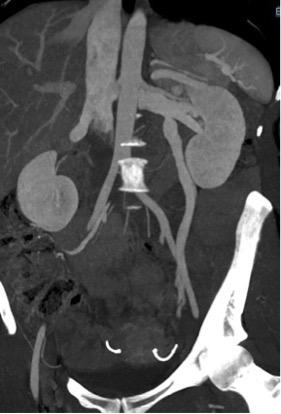

-       1er temps diagnostic : phlébographie iliaque interne,  veine rénale, veine gonadique

-       2ème temps thérapeutique : embolisation (points de fuite veineux pelviens si ils existent et sont symptomatiques, varices pelviennes et veine gonadique gauche). Matériel d’embolisation variable (mousse sclérosante, colle biologique, coil…)

Figure 1 : phlébographie avant et après embolisation